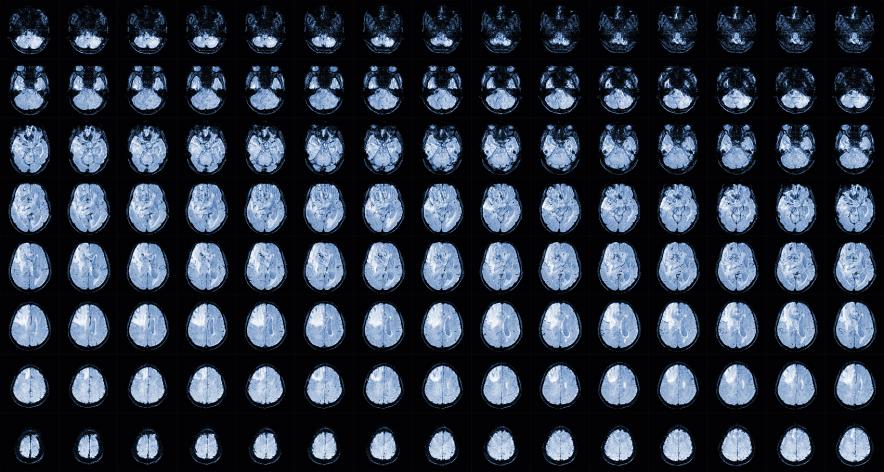

胶质瘤的临床表现在哪些方面

胶质瘤的临床表现,昆明肿瘤医院如何治疗胶质瘤-昆明医科肿瘤医院胶质瘤是一种常见的原发性脑肿瘤,其临床表现与肿瘤的大小、位置和病理类型有关。本文将介绍胶质瘤的临床表现。头痛头痛是胶质瘤最常见的症状之一,约有50%的患者会出现头痛。头痛通常是间歇性的,而且常常在早...

胶质瘤的症状,昆明治疗胶质瘤去哪家肿瘤医院-昆明医科肿瘤医院胶质瘤是一种常见的神经系统肿瘤,它起源于大脑和脊髓的胶质细胞。这种肿瘤可以是恶性的或良性的,并且可以在任何年龄段发生,但通常在成年人中更常见。本文将讨论胶质瘤的概述,包括其类型、症状和治疗。胶质瘤可以...